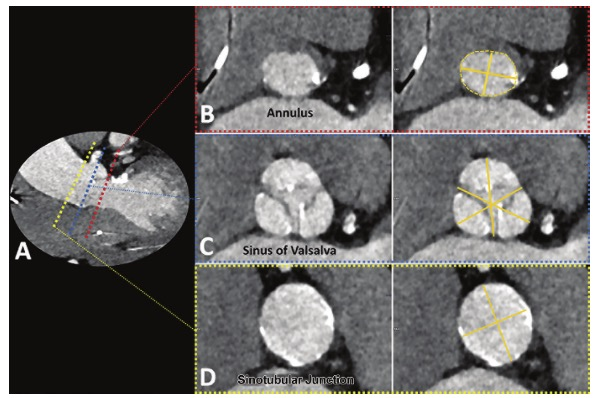

主动脉根部的详细分析

用于TAVR规划的CT数据集必须结合尽量避免瓣膜运动的主动脉环的可视化,

研究证明对于TAVR术前的主动脉瓣的测量最好是CCTA的收缩期,

对于TAVR术前的CTA扫描,扫描范围需要从锁骨下动脉开始延伸到股动脉。

在主动脉根部水平,测量的参数包括

-

主动脉环(aortic annulus) -

瓦尔萨尔瓦窦(sinuses of Valsalva) -

窦管(sino-tubular)连接

的尺寸。

A :不同主动脉根测量的参数的横截面的位置

B:主动脉环(aortic annulus)的长径和短径(实线),周长和面积的区域(虚线)。

C:瓦尔萨尔瓦窦(sinuses of Valsalva)三条尖端到连接(cusp-to-commissure)的测量线(实线)。

D:窦管(sino-tubular)连接的长径和短径(实线),上述数值代表主动脉环到左右冠状动脉开口的距离。

独立解决方案(3mensio)和多家供应商(Vitrea、GE HealthCare)现在提供特定于TAVR的软件包,可简化上述参数的测量。

Lotus这里帮大家找到了一篇基于GE平台的TAVR软件测量的教程,感兴趣的同学可以操作一下。

如果没有半自动化的后处理工具,相关技术人员必须能够手动获得所有必要参数的测量——包括选择植入瓣膜所需的主动脉环的长轴直径、短轴直径、周长和面积。

此外,TAVR的术前分析最好还应包括瓣膜形态特征、瓣膜和(主动脉)环的钙化定量和分布、冠状动脉开口高度和手术期间使用的估计的最佳C臂投影。